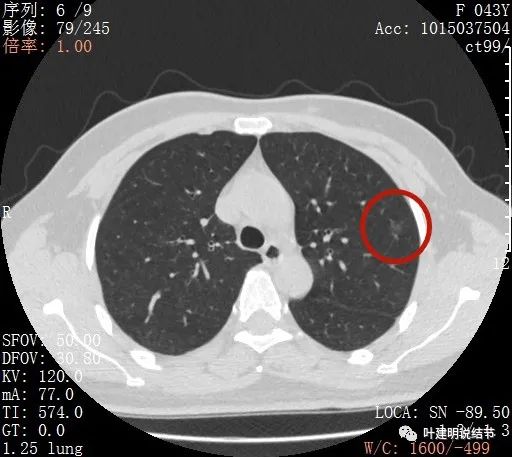

不均质的偏低密度磨玻璃结节,轮廓清

上图示病灶内部有高密度点状成分(粉色箭头所指)

同样示内部点状高密度,瘤肺边界清,密度显乱

上图显示混合磨玻璃结节,中间点状高密度区域,边上有微小血管征

上图示病灶边缘磨玻璃成分有的区域密度过低(绿色箭头),事后回头来看,磨玻璃部分的密度过低,不容易是浸润性腺癌,而更符合原位腺癌

上图示瘤肺边界处显模糊(砖色箭头),病灶内部仍是有偏高密度的点状成分

上图层面也显示病灶边缘欠清,有些模糊,虽总体轮廓还是比较清晰

从以上靶扫描图像上看,给人的印象是肿瘤范畴的结节,是混合磨玻璃结节,但磨玻璃部分的密度偏低,有的边缘显模糊,中间有点状高密度,也有微小血管进入,应该至少微浸润性腺癌可能性大。持续存在已经2月余,位置又还靠边上的,可考虑手术切除。下面再来瞧瞧后处理重建的图像: